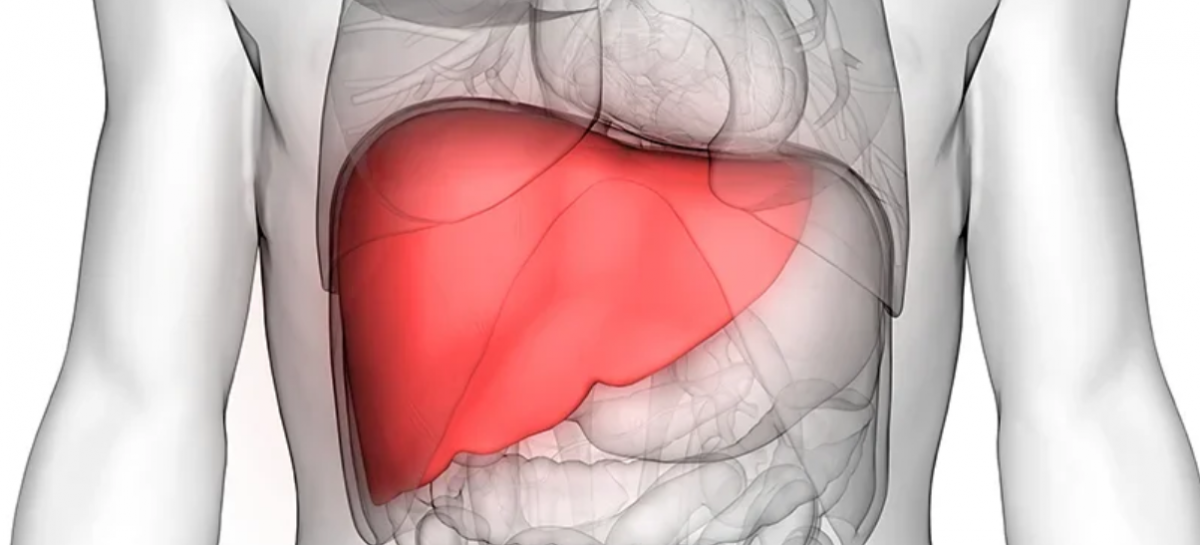

Impactul consumului excesiv asupra ficatului

Studiul, publicat în revista Clinical Gastroenterology and Hepatology, a examinat legătura dintre tiparele de consum de alcool și riscul de dezvoltare a leziunilor hepatice. Cercetătorii au definit consumul excesiv ca fiind ingestia a cel puțin patru băuturi alcoolice într-o singură zi pentru femei și cel puțin cinci pentru bărbați, cel puțin o dată pe lună. Rezultatele au arătat că persoanele cu astfel de obiceiuri au un risc de aproape trei ori mai mare de a dezvolta fibroză hepatică avansată, comparativ cu cele care consumă aceeași cantitate totală de alcool într-un mod mai moderat.

Fibroza hepatică, caracterizată prin acumularea de țesut cicatricial în ficat, reprezintă o etapă importantă în evoluția bolilor hepatice. Mai mult, cercetarea a evidențiat o legătură directă între cantitatea de alcool consumată într-o singură ocazie și gradul de afectare hepatică. Cu cât consumul este mai mare într-un interval scurt de timp, cu atât crește severitatea leziunilor.

Însă, autorii studiului subliniază că aceste rezultate pot fi relevante pentru populația generală. „Consumul unei cantități mari de alcool într-un interval scurt poate depăși capacitatea ficatului de a procesa alcoolul și poate declanșa inflamație, favorizând, în timp, apariția fibrozei”, a explicat dr. Brian P. Lee, coordonatorul studiului și specialist în transplant hepatic de la Keck Medicine.